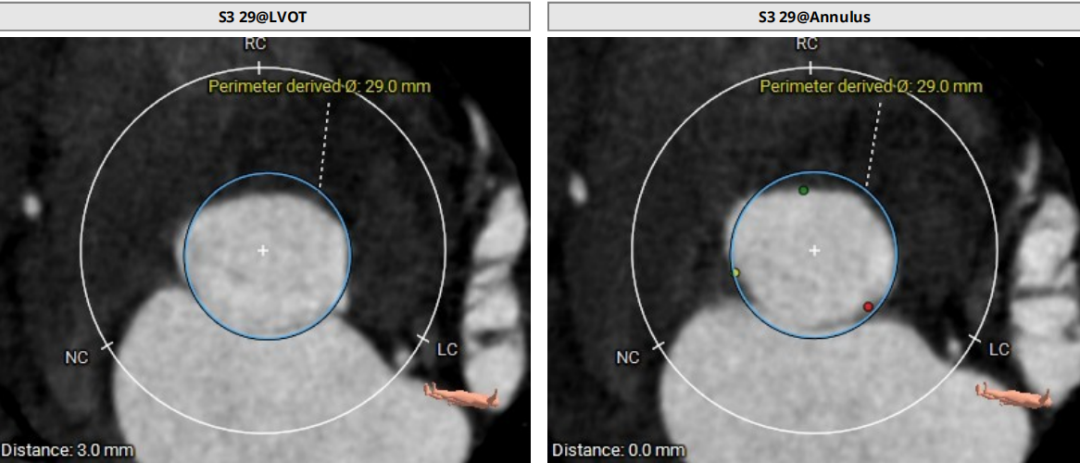

模拟29mm瓣膜植入情况:

78岁男性患者,主动脉瓣重度反流,瓣环面积约578.0mm²,折算瓣环直径27.1mm,LVOT约618.8mn折算直径28.1mm,轻度横位心,腹主动脉-降主动脉段迂曲,同时合并心功能不全,肺癌手术,属于外手术风险高危患者。经手术团队综合评估,患者为纯反流病例,瓣叶增厚并不明显且LOVT面积更大,仅瓣叶交界有少量钙化,对瓣膜锚定径向支撑力的要求很高,经过团队反复讨论,实施模拟分析后,拟行经导管TAVR术,拟以右侧股动脉为主入路,拟入29#SAPIEN3瓣膜,术中拟+3cc释放来实现oversize22%,于80/20位置释放,通过瓣环和瓣交接钙化实现瓣膜锚定,视情况选择是否后扩。